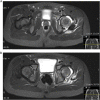

Recurrent traumatic hip dislocation in an 8-year-old boy

Pediatric traumatic hip dislocations (PTHD) are rare and represent around 5% of all pediatric dislocations. Associated bony or soft tissue injury can occur as often as 17%-25% of the time. We report a case of an 8-year-old boy presenting a posterior hip dislocation after a low-energy trauma, which was initially managed with closed reduction and bed rest for 1 week. Two days after hospital discharge, he suffered a recurrent posterior hip dislocation. He was now managed with 4 weeks of bed rest and lower limb skin traction followed by 1 week of no weight-bearing on crutches. With 6 months of follow-up, he is asymptomatic, walking autonomously, with complete and painless range of motion of the affected hip and no major radiographic changes. Pediatric traumatic hip dislocation is a rare and challenging injury that should be managed promptly. Currently, there is no protocol concerning treatment in the literature and its largely dependent of patient and parents' cooperation.